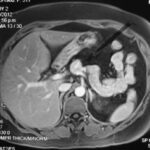

Paciente femenina de 48 años de edad que ingresa a Hospital Sanatorio Franchin por síntomas de cefalea y mareos, cuadro que se hace progresivo, presentando síncopes y posteriormente alteración del estado de conciencia. Los exámenes clínicos revelan una glucosa de 40 mg/dl, concomitante con insulina alta y péptido C elevado. Ingresa de forma programada para realización de duodeno pancreatectomía el 29 de mayo de 2021. Imágenes diagnósticas muestran estudio trifásico de tomografía de abdomen, lesión nodular en la cabeza del páncreas con ávido realce en fase arterial que en resonancia magnética se observa hiperintensa en T2, presenta restricción con la difusión y caída de la señal en el ADC. Además presenta realce tras la administración de contraste con gadolinio.

Ahora bien, como se mencionaba al principio, el estudio ecográfico es de muy baja sensibilidad y se identifique o no la lesión por este estudio, nuestro siguiente paso en el algoritmo diagnóstico de esta lesión es la tomografía. Esta es la prueba no invasiva inicial, con una sensibilidad del 63% al 83%, y detecta del 70% al 80% de los tumores. Esta debe realizarse como un estudio trifásico: fase arterial temprana a los 30 segundos, fase venosa a los 70 segundos, fase tardía de 3 a 5 minutos. La característica de estos tumores por tomografía es que se presentan como una masa sólida que tiene un ávido realce en la fase arterial, cuyo realce se mantiene y se observa más tenue en la fase venosa y en los tiempos tardíos la lesión se homogeniza.

La resonancia magnética es el otro estudio de imagen no invasivo que nos permite la detección de la lesión con una sensibilidad mayor que la de la tomografía, del 85% al 95%, donde los insulinomas presentan un realce tras la administración de contraste con gadolinio y secuencias T1 sin contraste son lesiones hipointensas y en secuencias T2 son hiperintensas.

La resonancia magnética confirmó aún más el diagnóstico de las lesiones ya previamente visualizadas en tomografía en esta revisión, con realce de las lesiones en secuencias T1 y contraste con gadolinio, y en las secuencias funcionales con restricción de la lesión y caída de la señal en el mapa de ADC.